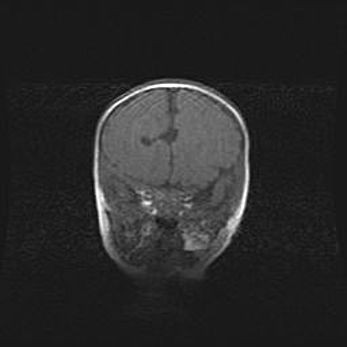

Сообщающаяся гидроцефалия. Кистозная энцефаломаляция головного мозга.

Возраст: 3 месяца 4 дня

Вес: 3100 г

Пол: женский

Окружность головы: 34 см

Срок гестации: 31 неделя

Кистозная энцефаломаляция головного мозга - одна из форм поражения головного мозга в детском возрасте. Характеризуется возникновением множественных и распространённых кист в коре, белом веществе и подкорковых образованиях головного мозга у плодов, новорождённых и детей раннего возраста. Развитие кистозной энцефаломаляции связано с внутриутробной асфиксией и гипотонией, родовой травмой, тромбозом синусов, пороками развития сосудов, инфекциями, сепсисом и другими причинами. Наиболее значимые инфекционные агенты: вирусы простого герпеса, цитомегалии, краснухи, токсоплазмы, энтеробактерии, золотистый стафилококк и другие.